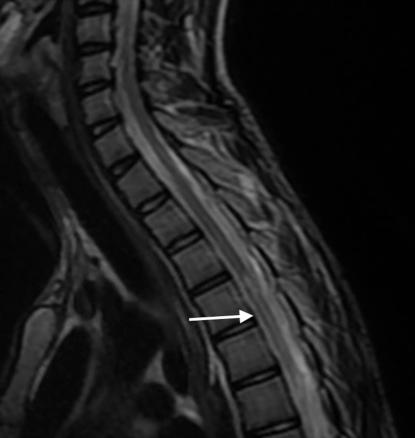

Une IRM médullaire est réalisée en urgence, mettant en évidence une anomalie de signal centromédullaire étendue de T4 à T6 en hypersignal T2 – réalisant un aspect en « œil de hibou » –, avec une restriction en diffusion et sans prise de contraste après injection de gadolinium (fig. 1).

Une IRM de contrôle est réalisée à J20, montrant une évolution de la myélite vers une cavitation avec atrophie médullaire (fig. 2).

L’installation brutale du déficit, l’absence d’anomalies associées et l’aspect radiologique sur les IRM initiale et de contrôle permettent d’évoquer une origine ischémique de cette myélite du territoire spinal antérieur.

Le diagnostic d’ischémie médullaire reste difficile à poser avec une IRM à l’aspect souvent normal de la moelle épinière sur les séquences T1 et T2. Si le tableau clinique évoque la possibilité d’une ischémie, les séquences de diffusion doivent compléter le bilan IRM. Les résultats de l’IRM de diffusion demeurent cependant aléatoires en raison d’une qualité d’image souvent insuffisante. Le contrôle IRM réalisé après vingt-quatre à quarante-huit heures confirme le diagnostic en visualisant un signal hyperintense en T2 de topographie centromédullaire de part et d’autre de la ligne médiane, correspondant au territoire de l’artère spinale antérieure (image en « œil de serpent » ou en « œil de hibou »). Au-delà de quarante-huit heures, l’IRM peut visualiser un effet de masse, et une prise de contraste est souvent observée. À la phase séquellaire, il est classique de noter une atrophie médullaire avec de petites cavitations intramédullaires de part et d’autre de la ligne médiane.1